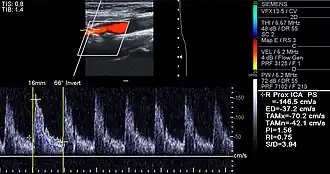

Carotid arteries supply blood to the brain and neck.[25] Marked narrowing of the carotid arteries can present with symptoms such as a feeling of weakness; being unable to think straight; difficulty speaking; dizziness; difficulty in walking or standing up straight; blurred vision; numbness of the face, arms and legs; severe headache; and loss of consciousness. These symptoms are also related to stroke (death of brain cells). Stroke is caused by marked narrowing or closure of arteries going to the brain; lack of adequate blood supply leads to the death of the cells of the affected tissue.[26]

Examples of anatomical detection methods include coronary calcium scoring by CT, carotid IMT (intimal media thickness) measurement by ultrasound, and intravascular imaging techniques, such as intravascular ultrasound (IVUS), and intravascular optical coherence tomography (OCT),[85][86] allowing direct visualization of atherosclerotic plaques.